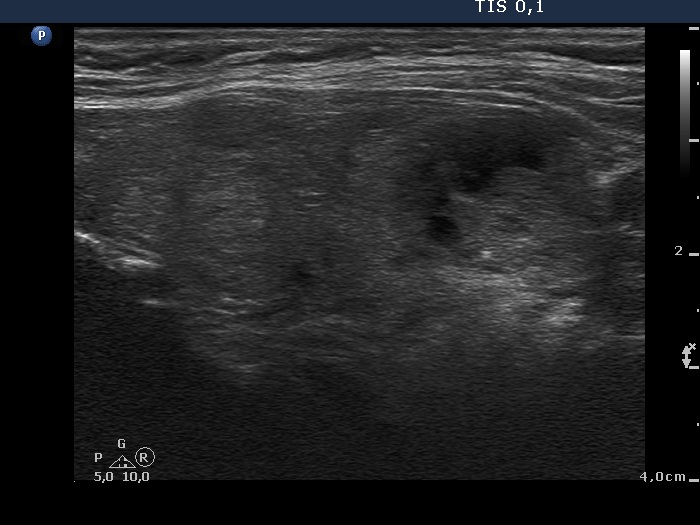

Study on 100 consecutive patients with thyroid nodule - case 061 (ultrasonographic picture 8)

Left lobe, longitudinal view.